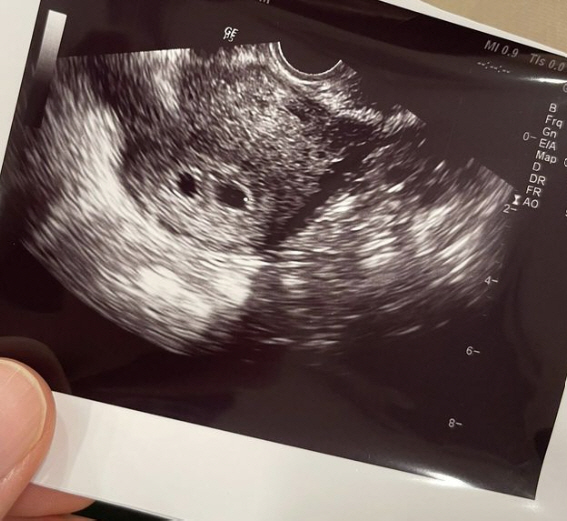

3일 윤한은 "경사가 났다!"라며 "오늘 오전에 아내와 함께 병원에 다녀왔다. 지난 시험관 시술을 통해 오늘 임신 확인을 받는 날이었다. 쌍둥이들이 찾아왔다!!"라고 전했다.